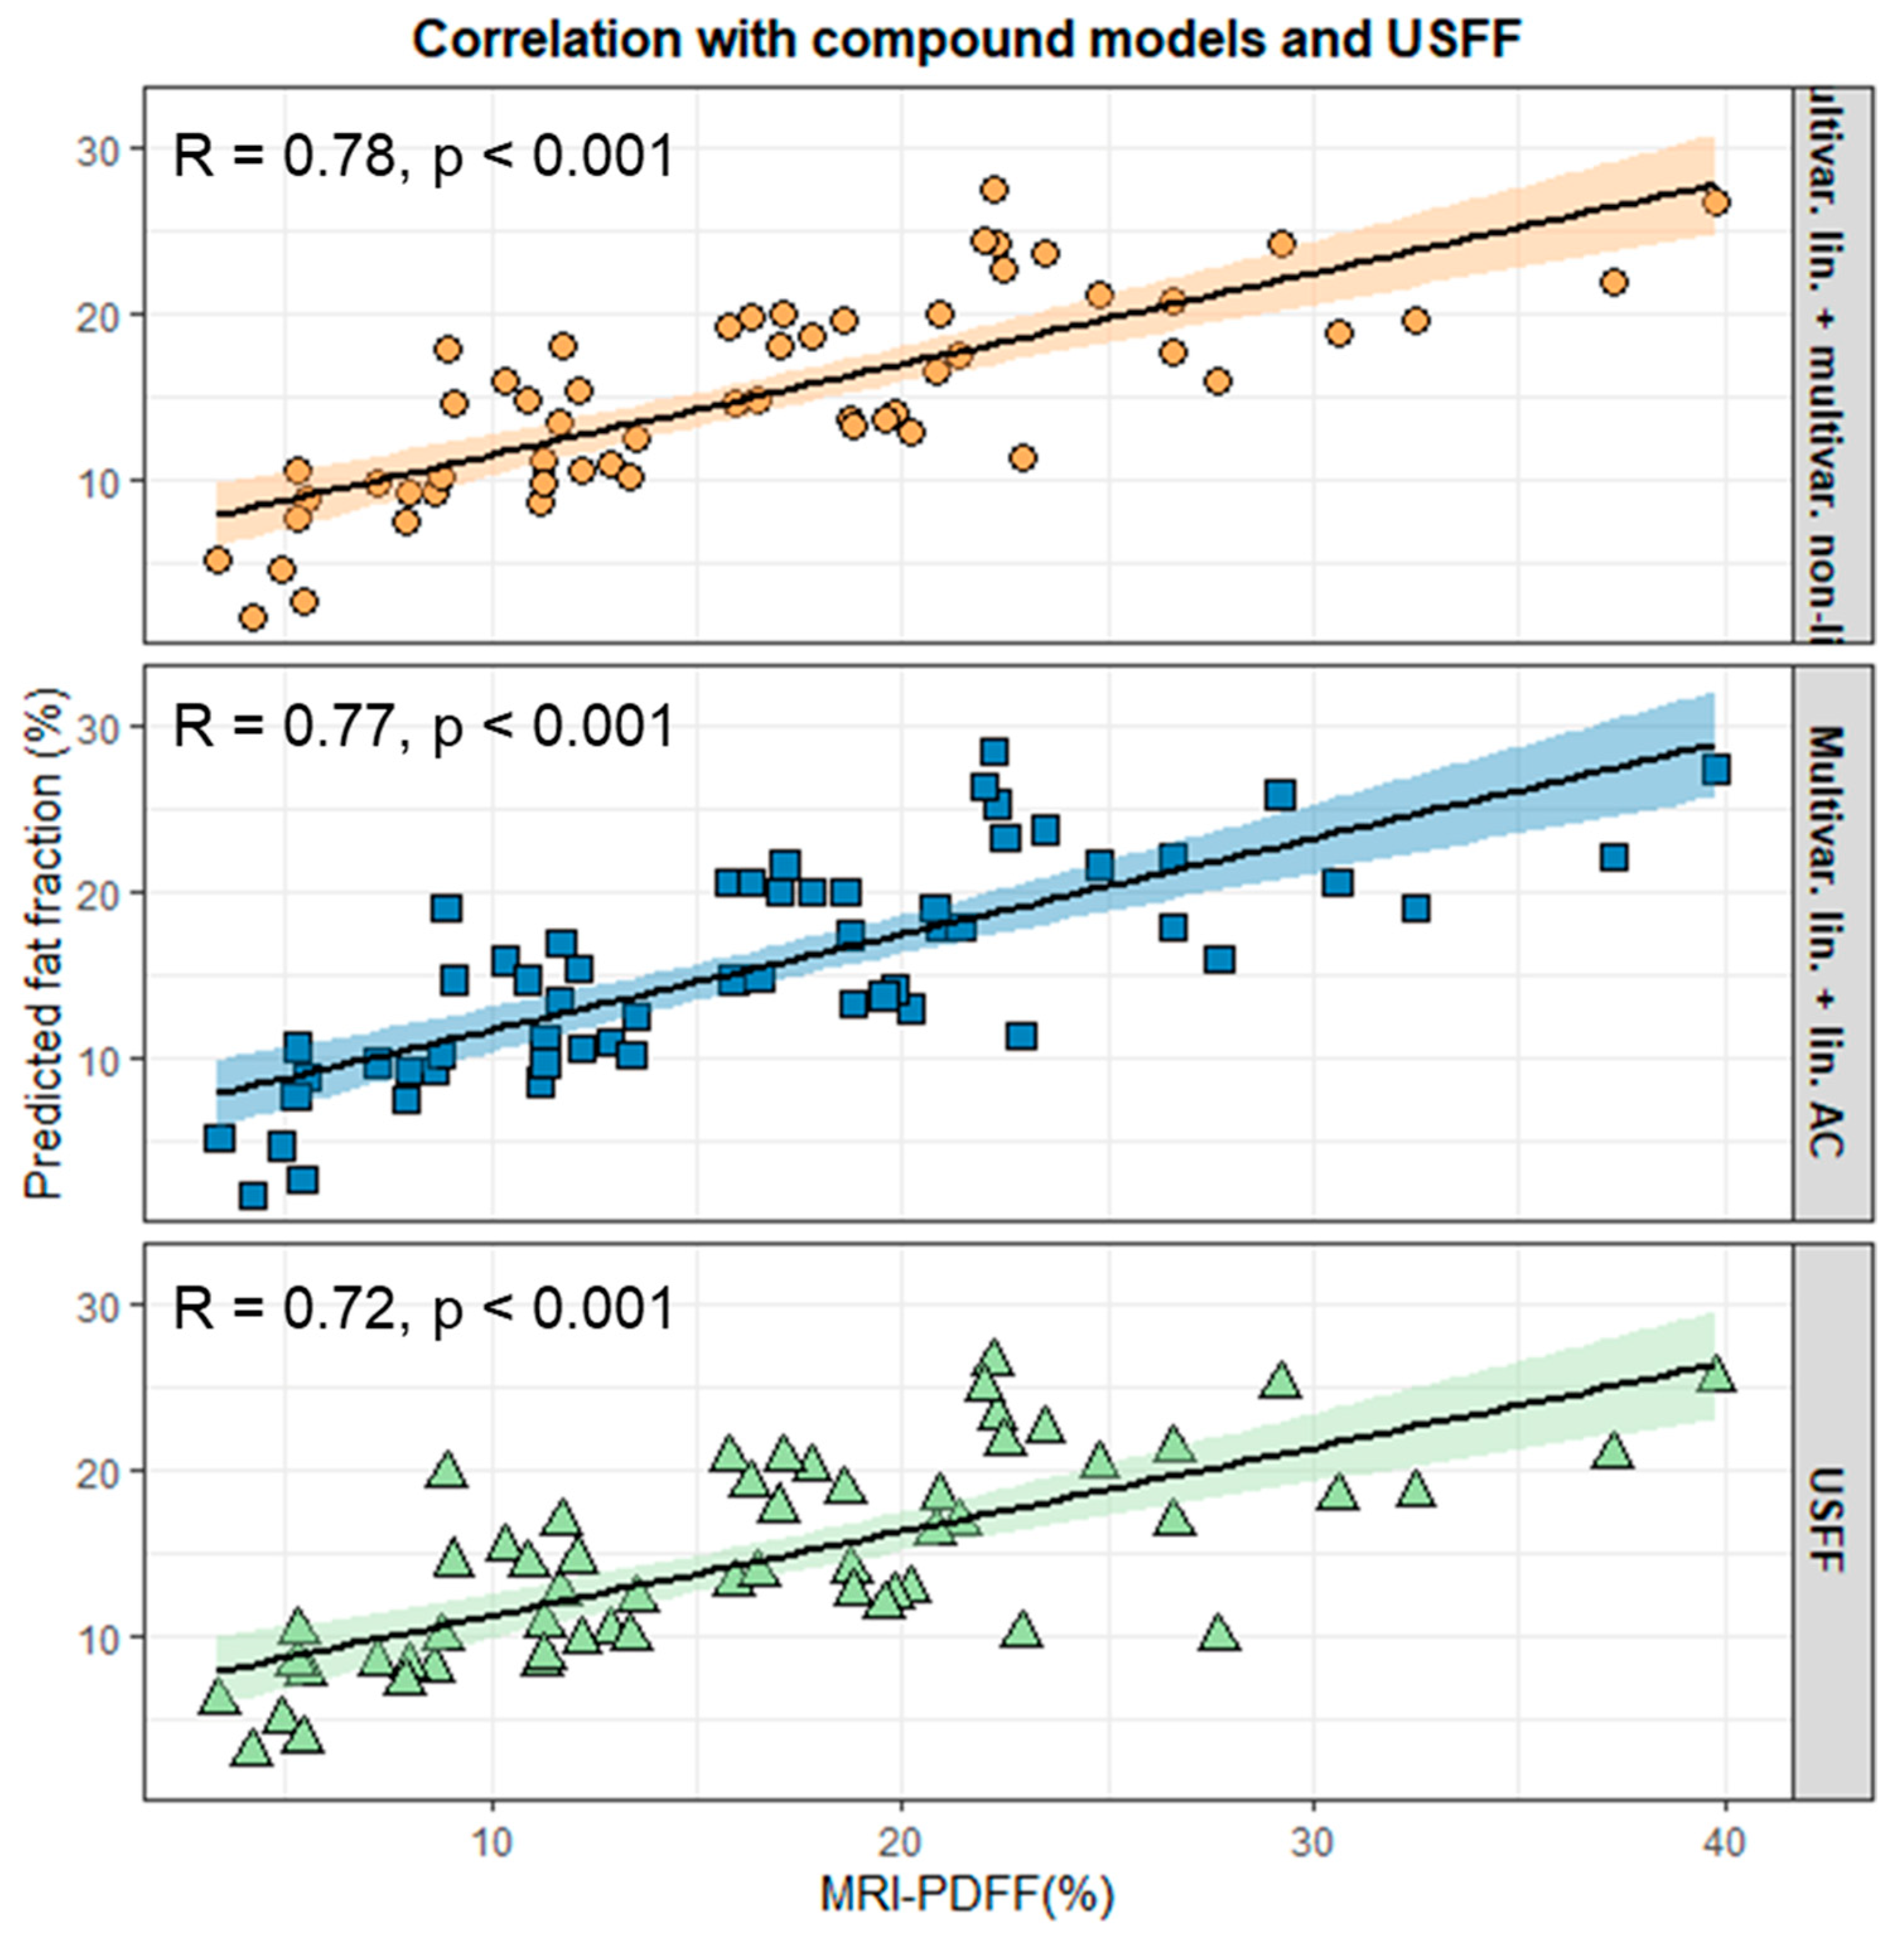

3.5. Construction and Validation of Compound Models

4. Discussion